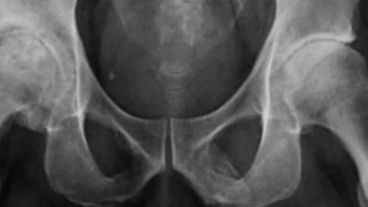

En las imágenes se mostraba una extensa calcificación de los tejidos blandos que forman el pene. Esto ocurre cuando se depositan sales de calcio en los tejidos blandos del órgano, provocando la aparición de placas de hueso donde no debería de haberlas. El caso es muy curioso y hay sólo 40 registros a nivel mundial según un informe médico publicado en la revista Urology Case Reports.